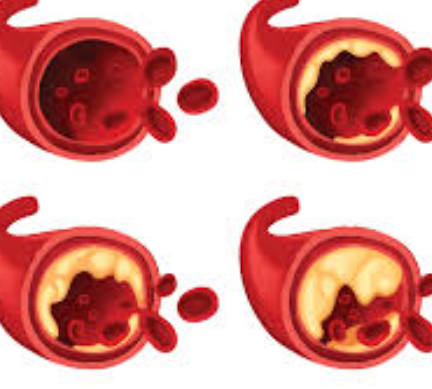

담석 원인

1. 담즙의 불균형

담석은 주로 담즙이 과도하게 농축되거나 담즙의 구성 요소가 불균형한 경우 형성됩니다. 담즙은 콜레스테롤, 담즙산, 담색소 및 세포 노화 물질로 구성되어 있는데, 이러한 성분들의 양이나 비율이 변화하면 담석이 발생할 수 있습니다.

3. 고지혈증

고지혈증은 혈중 콜레스테롤 수치가 높은 상태를 가리키며, 이는 콜레스테롤 담석의 위험 요인 중 하나입니다.

4. 담도의 이상

담도가 축수되거나 좁아지면 담석이 쉽게 형성될 수 있습니다. 담도의 이상은 선천적인 결함이나 염증, 감염 또는 외부 요인에 의해 발생할 수 있습니다.